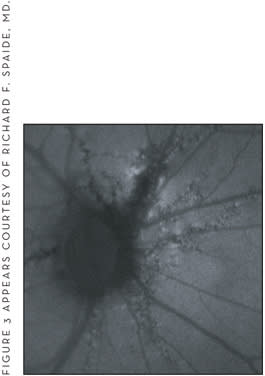

Regarding autofluorescence, angioid streaks appear as fissures with central hypoautofluorescence and with a variable amount of hyperautofluorescence at the borders of the cracks (Figure 3).11

Figure 3. This autofluorescence image shows the streaks as fissures with central hypoautofluorescence and a variable amount of hyperautofluorescence at the borders of the cracks.